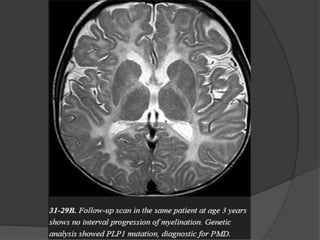

Hypomyelinating Disorders Pelizaeus-Merzbacher Disease X-linkeddisorder that results in nearly complete lack of myelination. One of the most common hypomyelinating disorders. 100% of classic PMD cases occur in males. PMD is typically identified in infants under one year of age. Imaging The typical imaging appearance of PMD is nearly complete lack of myelination. The entire cerebral WM appears strikingly and homogeneously hyperintense on T2WI.

• 55.

Preserved myelin aroundperivascular spaces gives the WM a "tiger" pattern. Hyperintensity of the pyramidal tracts or entire pons is typically present. Progressive WM and cerebellar volume loss are common.